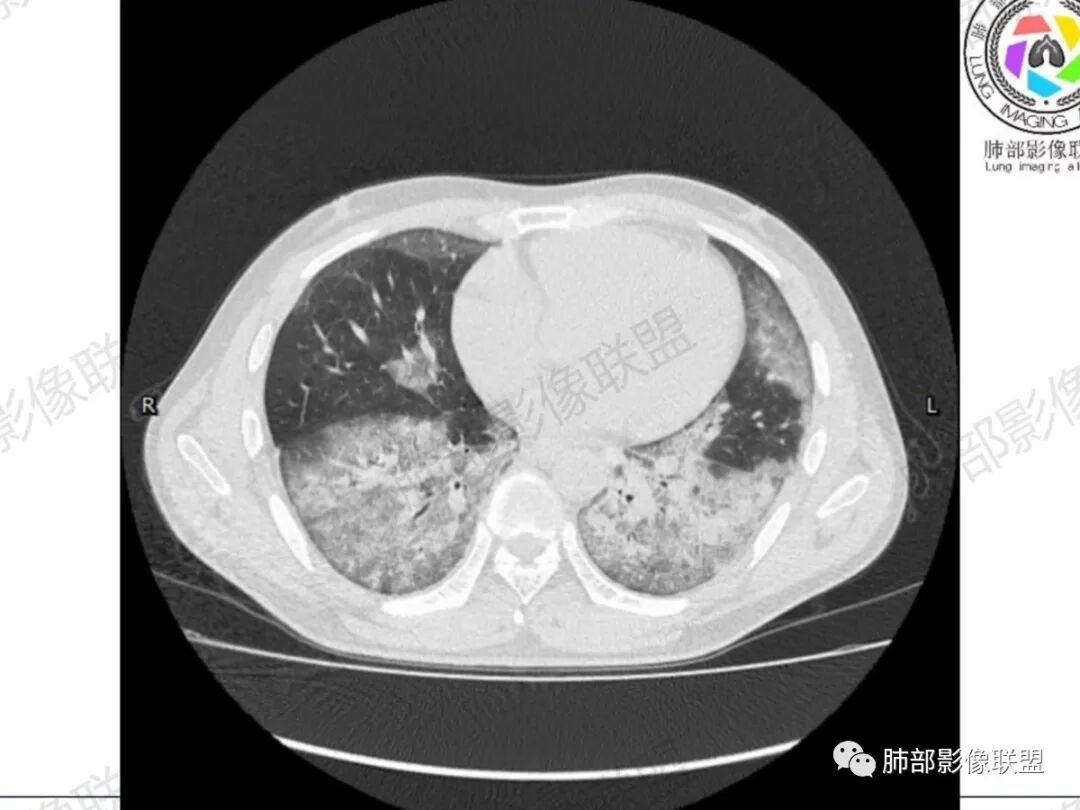

小兜:男,34岁,急性病容,临床症状进展快,双肺早期CT可见少量磨玻璃影,四天后复查进展迅速,双侧对称胸膜下为主,双下肺为重,对症治疗效果不佳,考虑中毒所致,百草枯可能

一切∮随缘:第一次CT双肺弥漫小结节,密度较淡,间隔4天后,双肺弥漫性渗出及间质增厚,以胸膜下及下肺为主,部分伴有重力作用,临床症状较重,考虑AIP,ARDS?重症结核?

宇宙:初次CT两肺纹理模糊,4天后进展迅速,两肺弥漫磨玻璃影,两肺外周及下叶胸膜下为主,与正常肺组织分界清,心影增大,支持百草枯中毒

1.双肺病灶从无到有,进展迅速,沿胸膜下分布磨玻璃密度为斑片影,较均匀,边界较清楚,呈镰刀状,近乎对称,期间可见细网格,符合较典型百草枯中毒肺影像学表现。